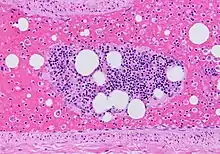

![]() | |

| Microscopic section of the lungs showing a blood vessel with fibrinoid material and an empty space indicative of the presence of lipid dissolved during the staining process. Haematoxylin and eosin stain | |